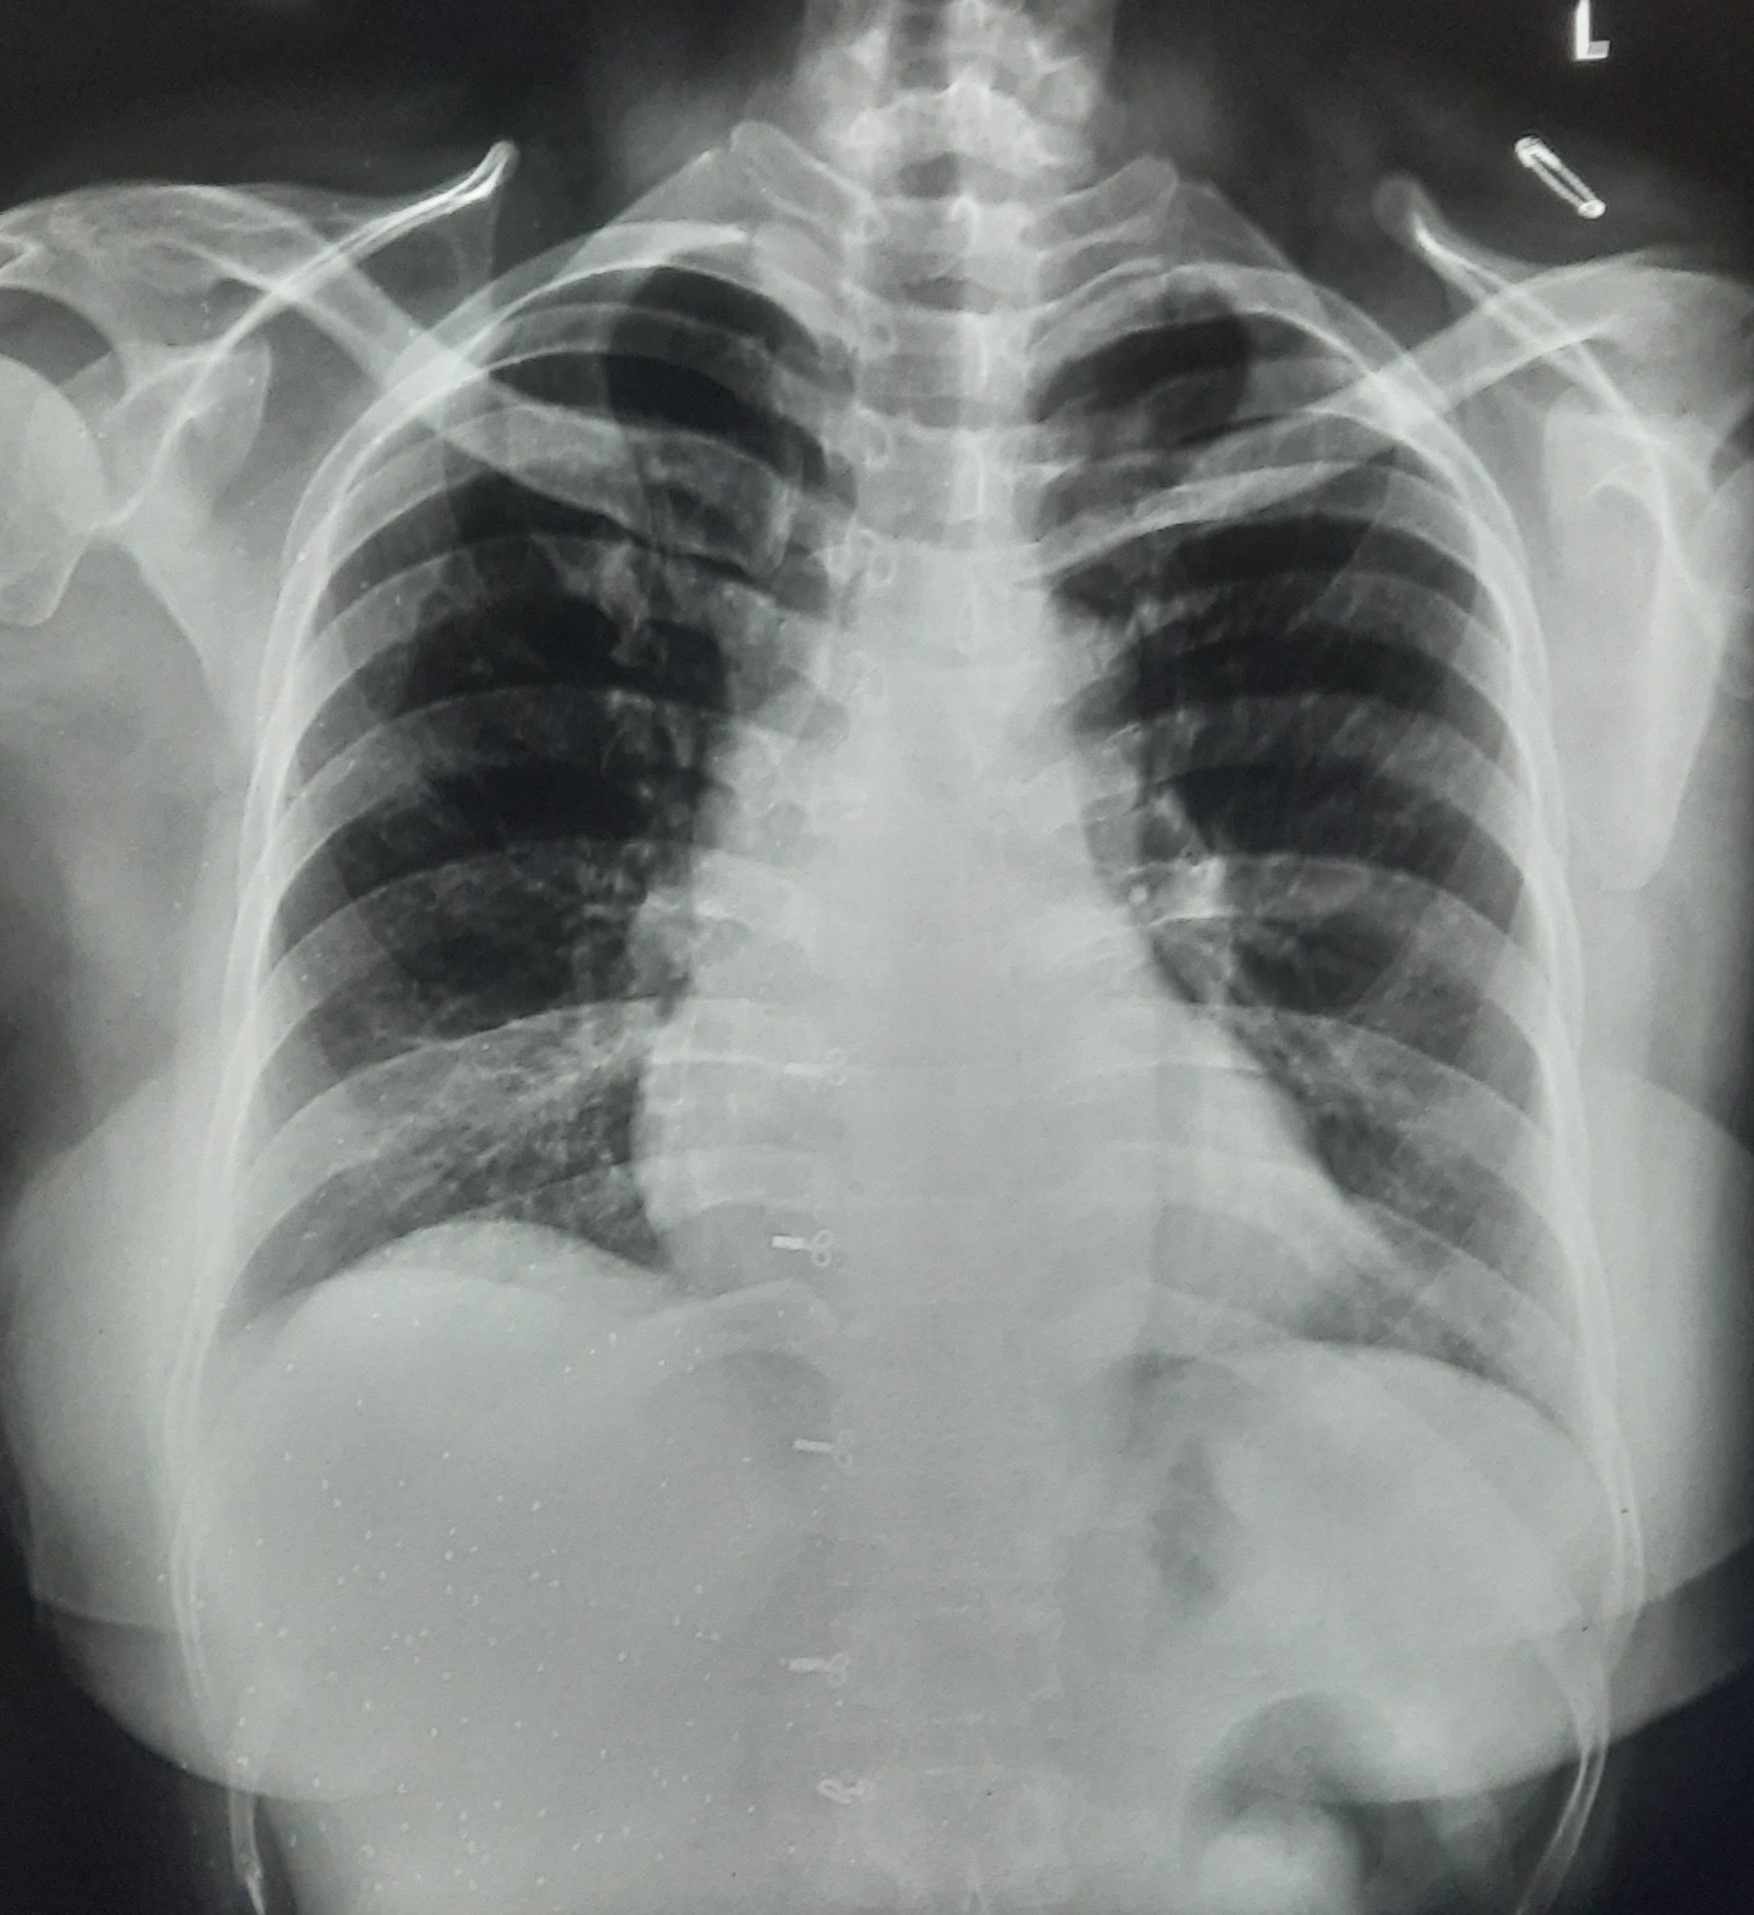

| 283 | IGGMC, Nagpur, Nagpur | P2 | 29-4189 Follow-up of 29-3923 |

Monali Pralhad Milmile | Consent taken on Paper | 46 Yrs. |

Provisional Diag : PTB Follow-up

Final Diag : Pleural Effusion |

TB Case (Confirmed) | Right Sided Upper Zone Fibrotic Lesion, Tracheal Pull Left side, Right sided & Left Sided Pleural Thickening Present, Right sided & Left Sided CP Angle Blunting Present, | Abnormality visible on x-ray |